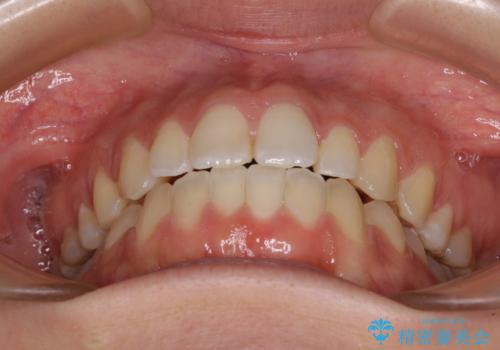

【モニター】オープンバイトをインビザラインで矯正治療

- 前歯の上下スペースによる食べにくさを気にして来院された患者様です。

インビザラインにより上下の前歯の隙間を閉じていくこととしました。

前歯のデコボコの解消と並行して上下の奥歯を圧下させるようにすることで、前歯を接触させるように計画しました。

上下の隙間に舌が入り込むことがオープンバイトの原因であったため、舌の筋肉のトレーニングも並行して行い、後戻りの抑制を図りました。